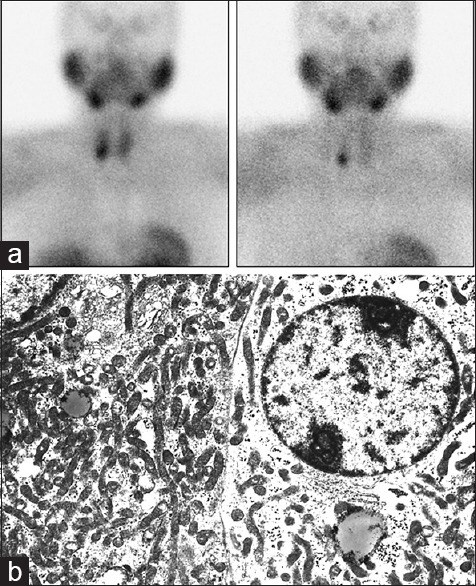

The aim of this study was to correlate the uptake of 99mTc-methoxy-isobutyl-isonitrile (MIBI) with ultra-structural features of parathyroid adenomas. Twenty patients with proven primary hyperparathyroidism were evaluated prospectively. Preoperative double-phase 99mTc-MIBI scintigraphy was performed in all patients and the degree of tracer uptake by the parathyroid lesions was assessed visually and semi-quantitatively. The excised glands were examined histologically and ultrastructurally, and their features were correlated with the degree of the radiotracer uptake. At surgery, 21 parathyroid adenomas were removed (double adenoma in one patient and a solitary adenoma in each of the remaining 19 patients). 99mTc-MIBI scan detected 18 of the 21 adenomas. There was positive correlation between the degree of 99mTc-MIBI uptake and the mitochondrial contents of the parathyroid adenoma cells. Four adenomas with intense uptake had high content of mitochondria in the cells. The three false-negative scans had low-to-moderate mitochondrial content. 99mTc-MIBI uptake is related to the mitochondrial content of the parathyroid adenoma cells.

Figures